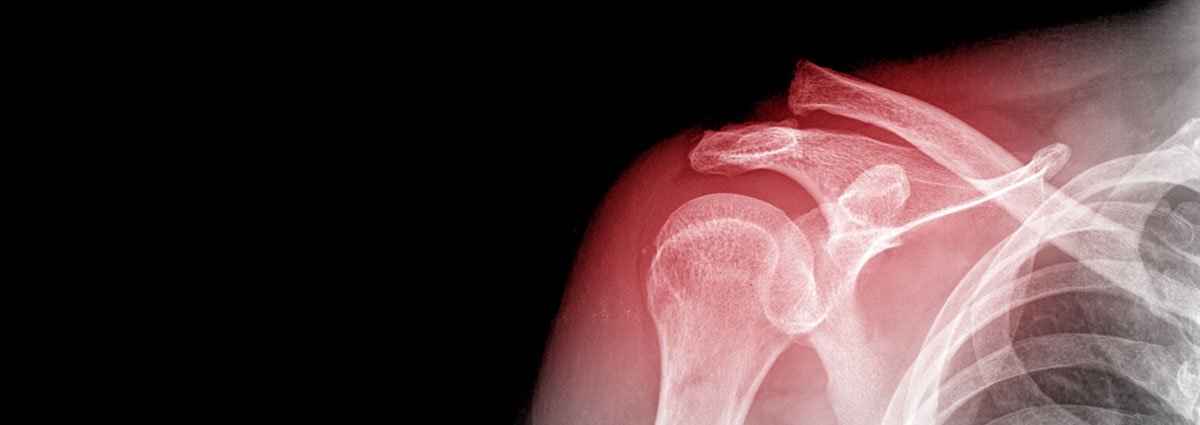

After an initial examination, the specialist may request diagnostic tests (X-ray, MRI, etc.) to confirm the diagnosis and determine the treatment to be followed, depending on whether the patient is dealing with:

- Fracturas

Las fracturas son lesiones producidas por un traumatismo de mayor intensidad que origina una rotura del hueso. Las fracturas en la articulación del hombro se pueden producir en cualquiera de los 3 huesos que lo forman:

- Fractura de la clavícula: suelen producirse por una caída sobre el hombro, el cual transmite la fuerza deformante hacia la clavícula produciendo su fractura.

- Fractura de la escápula u omóplato: son poco frecuentes y se suelen producir en traumatismos de gran energía en los que se ven afectados hombros, tórax y columna.

- Fractura de la cabeza humeral: también implican un traumatismo de gran energía. Esta lesión se da con más frecuencia en gente de edad avanzada debido a la disminución en la densidad ósea.

El daño y el tipo de fractura marcarán el tratamiento a seguir (reposo, medicación, etc). Si la fractura es grave, será necesaria una intervención quirúrgica para colocar de nuevo los huesos en su posición normal.